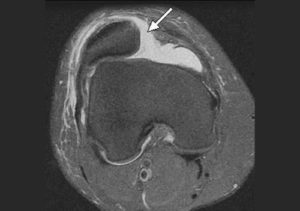

Чаще всего при первичном вывихе надколенника, если нет повреждения иных структур коленного сустава кроме медиального удерживателя надколенника, положительный результат дает консервативное лечение, которое заключается в иммобилизации коленного сустава в удобном прямом ортезе в течение 3 недель с момента травмы. При наличии в полости коленного сустава большого скопления крови (неизбежное, к сожалению, в случае острых травм) грамотный травматолог-ортопед выполнит пункцию коленого сустава с строгим соблюдением асептики и антисептики.